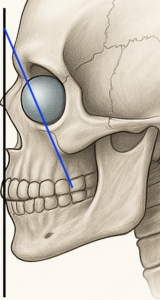

3D CT Findings in NOV

Vector Correction Strategy

Rather than simply adding volume, the implant is designed to reposition skeletal support:

- Converts a negative vector to neutral or slightly positive

- Advances the infraorbital support structure to match or exceed globe projection